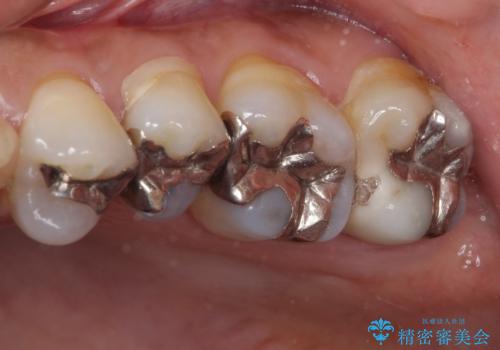

- 上下の奥歯にものが挟まりやすいことを気にして来院された患者様です。

上下ともに、やや大きいむし歯があり、そこにものが挟まりやすくなっていました。

上顎の奥歯は神経にまで虫歯が及んでいる可能性が高かったため、抜髄や断髄の可能性を考慮しながら処置を進め、セラミッククラウンにて補綴することとしました。